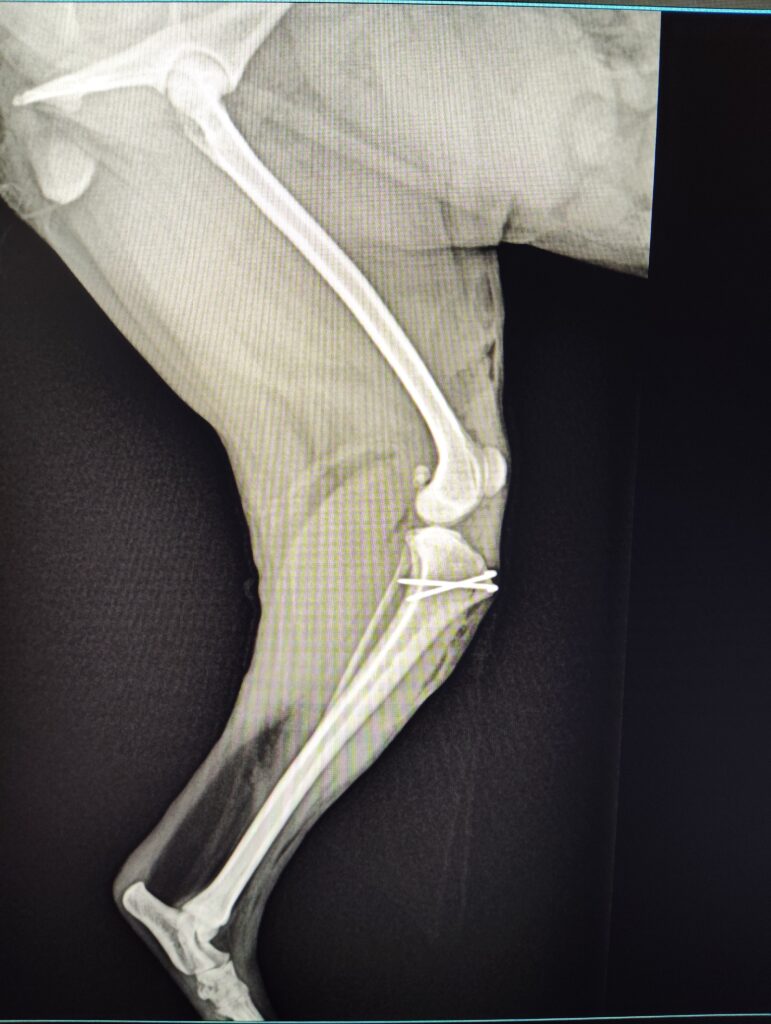

【レントゲン検査】

・左膝蓋骨内方に偏位